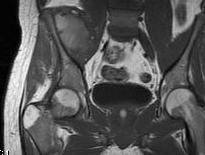

Pelvis

| Iliac crest | Ilioinguinal approach |

| Anterior column | Watson - Jones through G medius |

| Posterior column | Kocher - Lagenbeck through G maximus |

| Pubis | Pfannenstiel approach |

| Ischium | Posterior approach |

| Sacrum | Direct posterior approach |